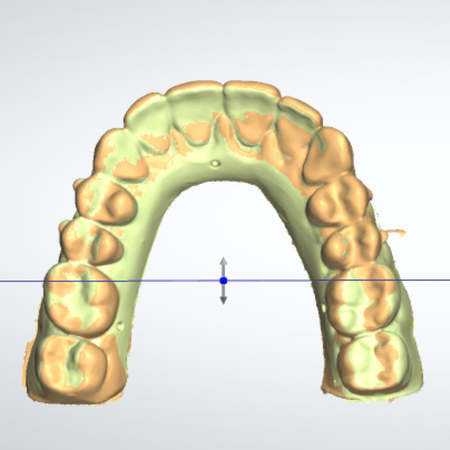

Impact of different levels of diastema and crowding on the precision of 3D-printed dental models: a comparative analysis using digital superimposition

Introduction: This study aimed to evaluate the impact of varying degrees of anterior diastema and crowding on the precision of 3D-printed dental models using digital superimposition techniques. Materials and Methods: A digital maxillary...

diastema Digital orthodontics 3D-printing Dental crowding Dimensional precision Digital superimposition

Objective: This study aimed to analyze the dimensional stability of 3D resin-printed models for orthodontic aligners under specific storage conditions over a period of up to six months. Methods: A model of the upper arch of a dental mann...